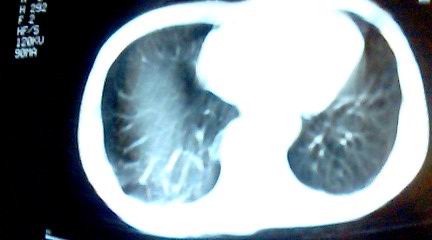

标题: CT25218:请教!胸部CT,胸8椎体骨质破坏,伴周围软组织肿。 [打印本页]

标题: CT25218:请教!胸部CT,胸8椎体骨质破坏,伴周围软组织肿。

患者,女41岁,肢体乏力。

双肺及胸椎结核。

双肺及胸椎结核。支持!

两肺上叶继发性肺结核;胸椎结核并椎旁寒性脓肿形成。